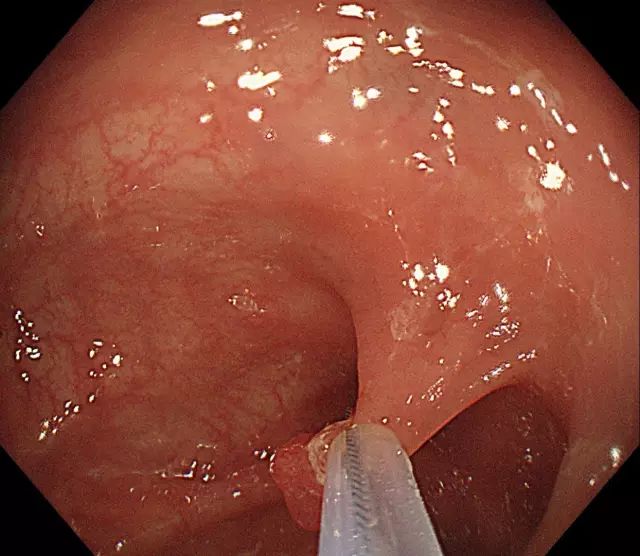

步骤四:轻轻向肠腔内提起息肉,使钢丝圈尽量远离肠壁黏膜。

图片

步骤五:在钢丝圈上脉冲式通高频电进行电灼烧,直至息肉根部被切断,息肉脱落。